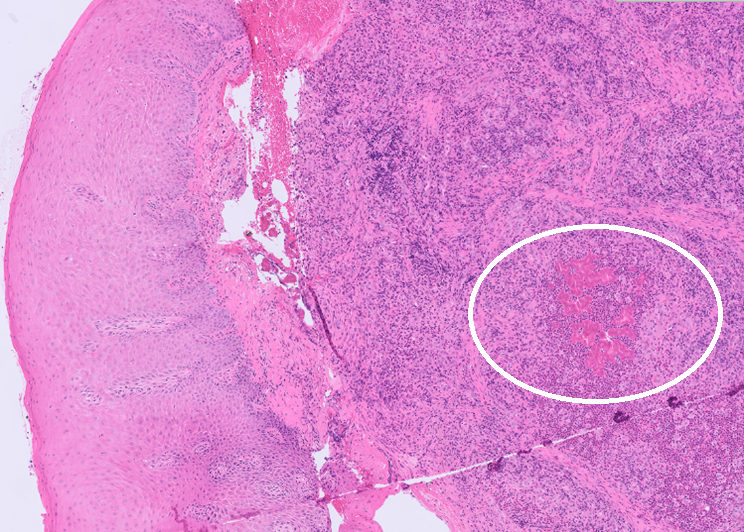

Within the submucosa of the oral cavity were large colonies of Gram-negative bacteria surrounded by bright eosinophilic hyalinized material forming radiating, club like projections (Splendore-Hoeppli material) (Figure 2). These were surrounded by large numbers of neutrophils, which were further surrounded by dense aggregates of macrophages, with fewer lymphocytes, and plasma cells. The overlying oral mucosa was intact, with no evidence of pustule, or vesicle formation.

Figure 2. Within the submucosa of the oral cavity are nodules of pyogranulomatous inflammation surrounding, brightly eosinophilic Splendore-Hoeppli material (circle), H&E 20x (left). Within the material, there are Gram-negative colonies of bacteria, Gram-stain 40x (right).